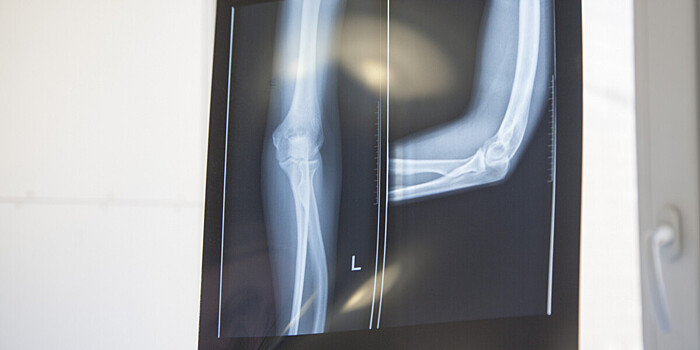

Ученые научились лечить переломы с помощью плазмы

Ученые из Осакского университета создали метод, который позволяет быстро сращивать переломы костей с помощью плазменного облучения.